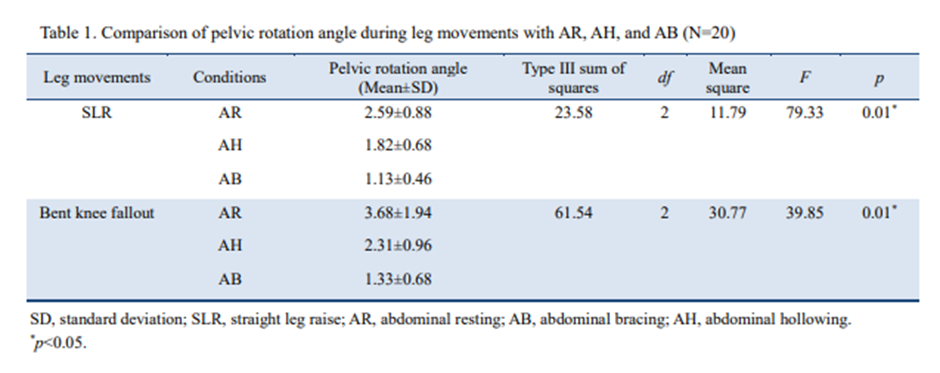

2020년도 연구논문에서는 다리의 무릎을 펴고 신전하는 Active Leg Raise(SLR)동작과

무릎을 구부리고 다리를 거상시키는 Bent Knee Fall out(KFO)동작수행시

Abdominal Hollowing과 Abdominal Bracing 그리고 휴식시를 비교한 논문연구를

언급해보려고합니다.

이 연구에서는 Abdominal Bracing방법이 Abdominal Hollowing방법보다 다리

신전거상(SLR)동작 수행시에 골반의 회전각도가 더 줄어들었다고 언급하고 있습니다.

물론 크레이그리벤슨선생님의 이 칼럼과 앞선 논문에서의 연구결과 에서처럼

Abdominal Bracing의 방법이 골반회전감소와 축강성(Axial Stiffnes)에 도움이 더 되고

Abdominal Hollowing방법은 그 효과가 적을수 있습니다.